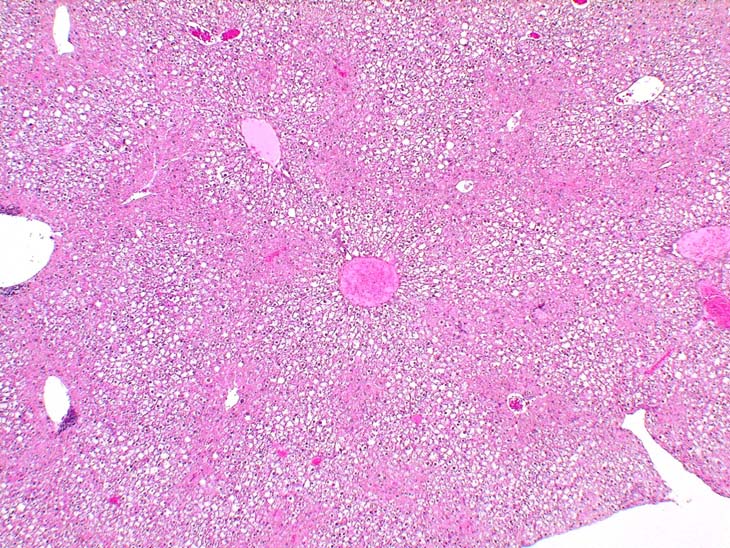

Centrilobular deposition of glycogen in a B6C3F1 mouse.